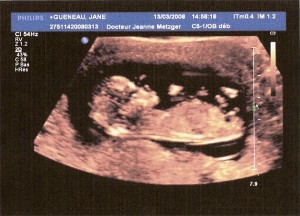

Second ultrasound – March 13, 2008

Hello world!

I like moving, and made some summersaults.

Mum & Dad think it’s like a “Saut de cabris” … I don’t know what that means but it must be cool, cuz Daddy cried of joy!

The doctor said that I was very active, did not stop calling me “Coco” but could not tell if I was a Girl or a Boy.

Size : 7cm Head to toe 😉